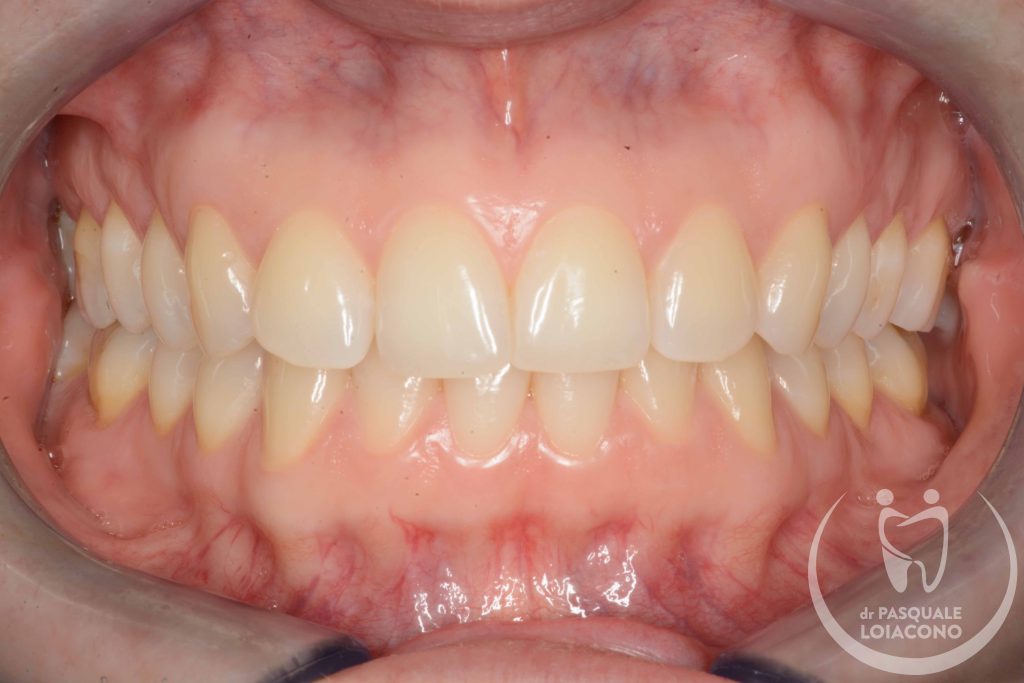

Quando ci sono problemi articolari della mandibola è necessario ricercare un’occlusione dentaria che rimetta il sistema il più possibile in equilibrio. L’organo della masticazione non è costituito solo da denti, ma anche da articolazioni e componenti neuromuscolari, e solo quando tuti i componenti sono in armonia tra loro si può avere salute e benessere. In realtà non tutti gli studiosi sono d’accordo su questioni fondamentali e non esiste visione unanime. Questo vuol dire che potreste incontrare un odontoiatra che sconsiglia qualsiasi trattamento, se non fisioterapia e massaggi o addirittura solo terapia psicologica di sostegno. All’opposto esistono scuole di pensiero che identificano nell’occlusione il fattore scatenante di una patologia che comunque resta complessa e multifattoriale. Da dentista desidero che la bocca funzioni bene e segua le regole stabilite, perché considero comunque positiva questa condizione, e quindi cerco di riportare l’occlusione del paziente verso una condizione il più possibile ideale.

Avere una occlusione stabile ed equilibrata non farà certamente più male che avere squilibri occlusali, anche se la Scienza non è ancora riuscita a mettersi d’accordo su quanto lo squilibrio occlusale disturbi il sistema della masticazione o su quanto influenzi la postura.

Nello studio del Dr Pasquale Loiacono si esegue diagnosi e terapia dei diversi problemi gnatologici, con terapie personalizzate protesiche, additive non invasive ed ortodontiche.